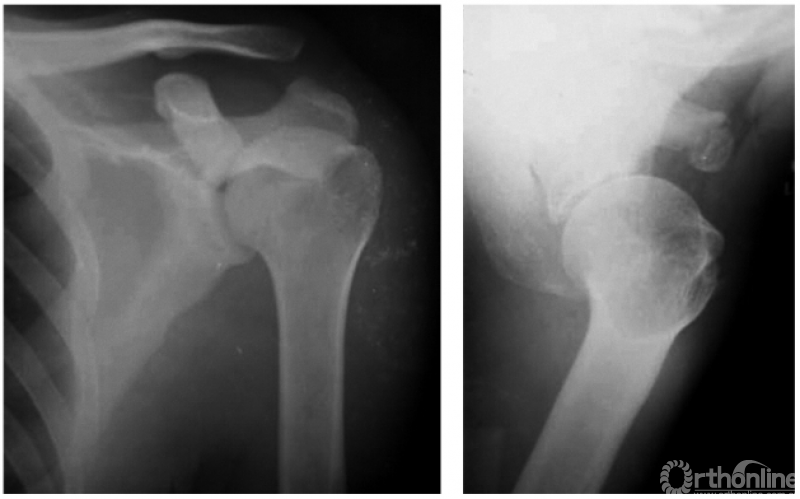

1. 肩锁关节脱位并喙突撕脱骨折

本例虽然肩锁关节发生脱位,但因喙突撕脱骨折而喙锁韧带未断裂,故喙锁间隙正常(图3)。